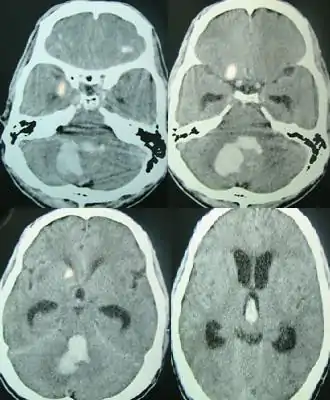

Hemorragia cerebral

Una hemorragia cerebral (también, hemorragia intracerebral, ICH) es un subtipo de hemorragia intracraneal producida en el cerebro. Puede deberse a un trauma cerebral o a un accidente. Se trata de una hemorragia intra-axial, es decir, una que se produce dentro del tejido cerebral[1] y no fuera de él. La otra categoría de hemorragia intracraneal es la de las hemorragias extra-axiales: por ejemplo, el hematoma epidural, el hematoma subdural y la hemorragia subaracnoidea, que ocurren dentro de la cabeza pero fuera del tejido cerebral.[cita requerida]

Las áreas del cerebro afectadas por la hemorragia quedan dañadas y, si se acumula un suficiente volumen de sangre en el espacio extravascular, se puede provocar una hipertensión intracraneal; la cuantía de la hemorragia determina la gravedad de este accidente vasculocerebral agudo. La tasa de mortalidad de estas hemorragias intraparenquimales es de más del 40%.[2]